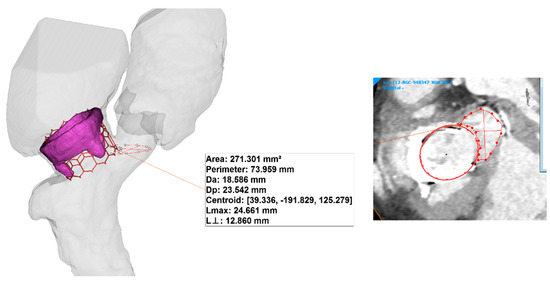

Figure 3 shows the relative position of THV in the heart anatomy as done according to the clinical guideline and cardiologist’s suggestion. The optimal implantation height of the THV on the bioprosthetic heart valve was with 1/3 of the height in the left ventricle. We found that the area of the neo-LVOT is about 271 mm2, and this value is quite higher than current clinical guidelines for TMVR. Indeed, we show that the neo-LVOT area is higher than the clinical cut-off of 100 mm2 [1], which is considered a predictor of adverse outcomes related to neo-LVOT. Bioprosthetic valve leaflets longer than the implanted THV can also lead to prolapse into the neo-LVOT or infolding into the THV. The risk of life-threatening neo-LVOT obstruction is exaggerated when the aortic and mitral annular planes are acutely angulated rather than parallel, when the interventricular septum bulges toward the LVOT and when the implant extends or flares into the left ventricle.

Figure 3.

3D model of the THV as virtually implanted in the heart valve bioprosthesis and dimension of the mitral valve annulus.